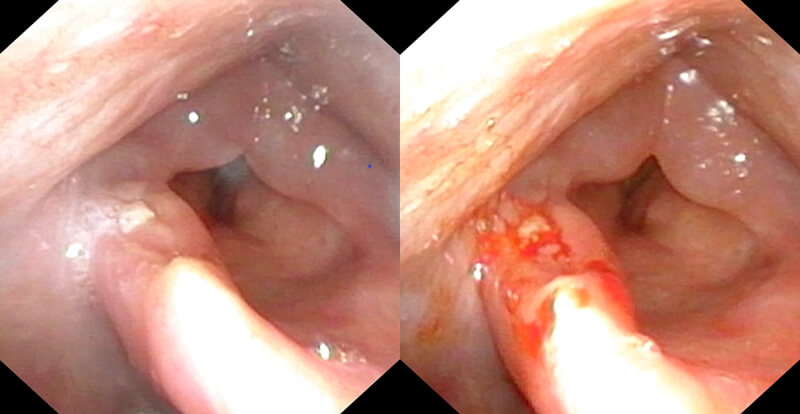

Pre and post biopsy.

The patient is instructed to make a prolonged ‘e’ sound to allow laryngeal gargling of the topical anaesthetic if the vocal folds are to be biopsied. After visualisation of the lesion, biopsies are performed using the flexible biopsy forceps (EndoJawTM Alligator jaw-step fenestrated 1.9mm FB-211D, Olympus Medical Systems Corp, Japan) which are passed down the endoscope channel. The biopsies are taken under endoscopic guidance by pushing the open jaws into the lesion, closing the jaws and pulling back swiftly on the forceps whilst holding the endoscope steady.

The specimen is then transferred into the pathology specimen container. Multiple biopsies can be taken using this method. Images were displayed using a video processor (CV-170, Olympus, Japan) which, in our case, allows both white light and narrow band imaging modalities. Photographs are taken pre and post biopsy and these are stored in the patient’s notes. There is also the facility to video record the procedure.